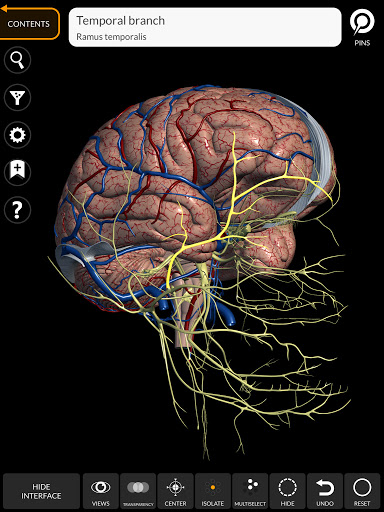

"Anatomy 3D Atlas" cho phép bạn nghiên cứu giải phẫu người theo cách dễ dàng và tương tác.

Thông qua giao diện đơn giản và trực quan, bạn có thể quan sát mọi cấu trúc giải phẫu từ mọi góc độ.

Các mô hình giải phẫu 3D đặc biệt chi tiết và có kết cấu lên đến độ phân giải 4k.

• Hệ thống thần kinh

TÍNH NĂNG •

• Xoay và phóng to từng mô hình trong không gian 3D

• Tùy chọn ẩn hoặc cô lập một hoặc nhiều mô hình đã chọn

• Chức năng đánh dấu để lưu chế độ xem tùy chỉnh

• Hiển thị/Ẩn giao diện UI (rất hữu ích với màn hình nhỏ)